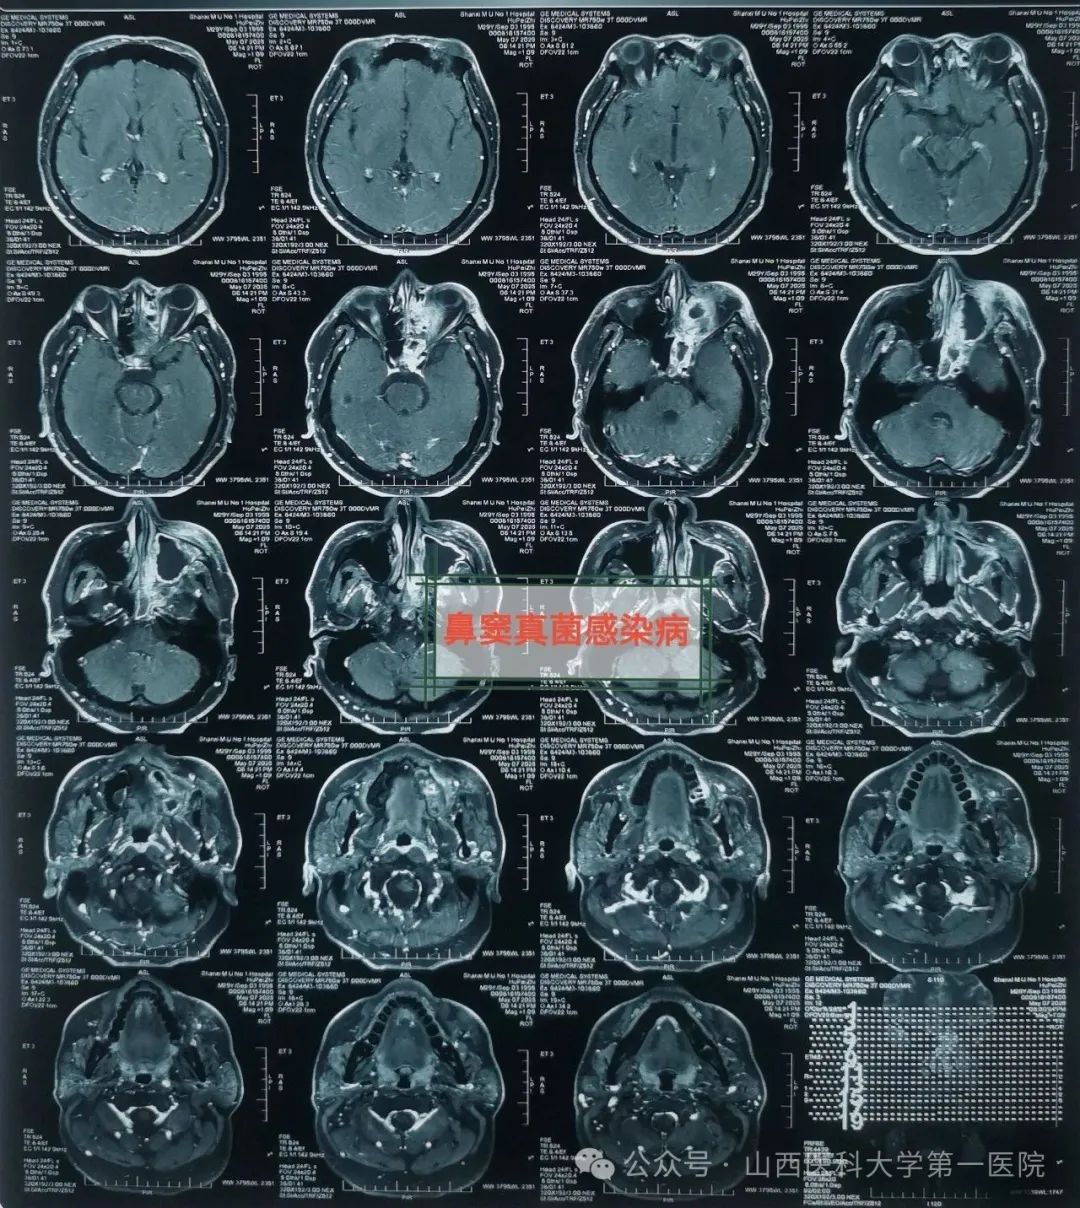

耳鼻咽喉-头颈外科,确诊为鼻窦真菌感染,医生通过手术切除鼻腔病变组织,清除霉菌团块,开放鼻窦,引流分泌物,清洗术腔,重建鼻腔结构、恢复功能,改善并缓解了临床症状。

耳鼻咽喉-头颈外科皇甫辉教授介绍,真菌性鼻窦炎是临床常见的特异性感染性疾病,近年来发病率有上升趋势,可能与抗生素广泛使用、环境污染等有关,而糖尿病、抗肿瘤药物治疗、放疗以及长期使用激素等是真菌性鼻窦炎的高发人群。真菌性鼻窦炎通常分非侵袭型真菌性鼻-鼻窦炎与侵袭型真菌性鼻-鼻窦炎两类,非侵袭型真菌性鼻-鼻窦炎之病变局限在鼻窦腔内,粘膜和骨壁内却无真菌侵犯;而侵袭型真菌性鼻-真窦炎是真菌感染不仅位于鼻腔,同时侵犯鼻窦粘膜和骨壁,并向鼻窦外周围结构和组织如眼眶、前颅底或翼腭窝等侵袭发展,一般情况下,侵袭型真菌性鼻-真窦炎预后凶险。

皇甫辉讲到,低免疫功能、低氧及高血糖环境是真菌生存合适条件,局部因素也是部分真菌性鼻窦炎主要致病因素之一,各因素所致鼻腔鼻窦通气引流受阻,解剖因素如中鼻道狭窄、中鼻甲反向偏曲等,局部炎症水肿,窦腔分泌物潴留,同侧上列牙齿病变等。真菌性鼻-鼻窦炎侵袭型者一经确诊,应尽早手术,清除鼻腔和鼻窦内真菌病原和坏死及不可逆之病变组织,恢复鼻腔鼻窦通畅引流,病变范围广者可采用柯-陆氏手术、与鼻内镜手术联合等术式,病变累及颅内时可采用颅面联合术式,术前应用抗真菌药物治疗,术后可应用抗真菌药物冲洗鼻腔和鼻窦等。